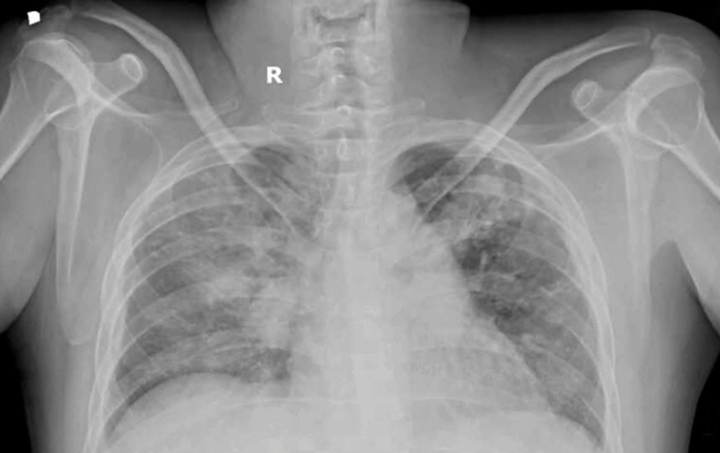

Bệnh nhân nhập viện trong tình trạng phù phổi cấp do quá tải dịch trên nền thận mạn giai đoạn cuối. (Ảnh: BVCC)

Qua thăm khám, bác sĩ chẩn đoán ông N. bị phù phổi cấp do quá tải dịch trên nền bệnh thận mạn giai đoạn cuối, kèm theo viêm phổi nặng, thiếu máu mạn, đái tháo đường típ 2 khó kiểm soát và rối loạn lipid máu.